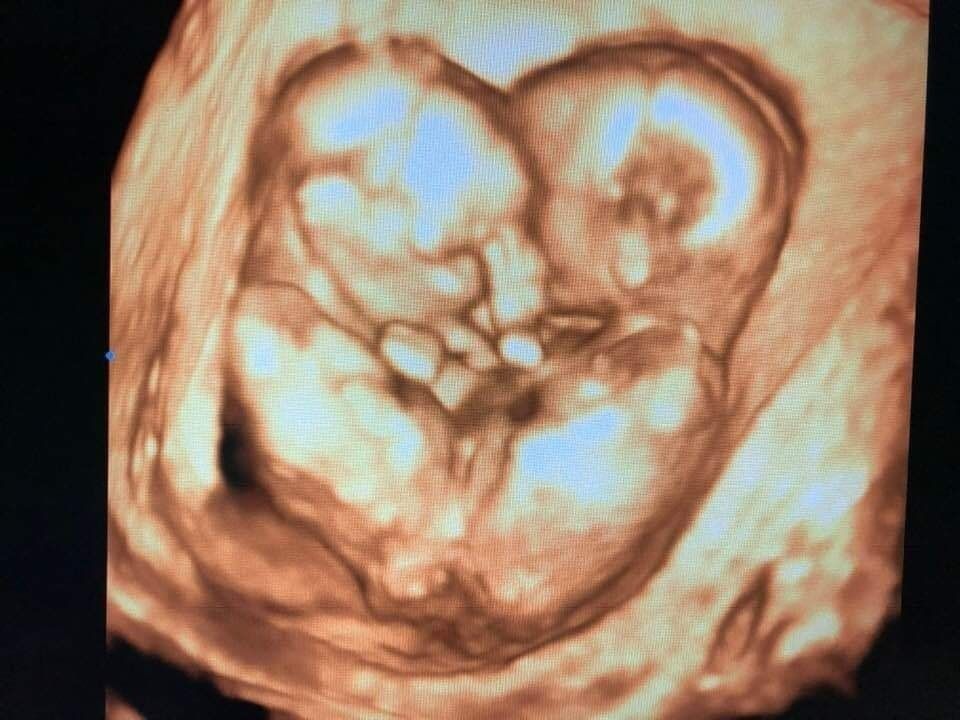

Chia sẻ với VietNamNet, bác sĩ Vũ cho hay lúc đang mang thai được 14 tuần 6 ngày, chị Hồng Thúy (26 tuổi, mẹ của hai bé "song Nhi") đến bệnh viện khám lần đầu. Bác sĩ Vũ là người trực tiếp siêu âm và phát hiện chị Thúy mang song thai dính vùng bụng chậu.

Khi nhìn thấy sự khát khao được giữ con của vợ chồng chị Thúy, anh rất xúc động. Anh quyết định đưa hình ảnh siêu âm hai bé gái dính liền lên trang cá nhân, kèm chú thích: “Chúng ta được sinh ra là nhờ sự can đảm của ba mẹ” làm kỷ niệm, một phần như để tiếp thêm sức mạnh cho vợ chồng chị Thúy.